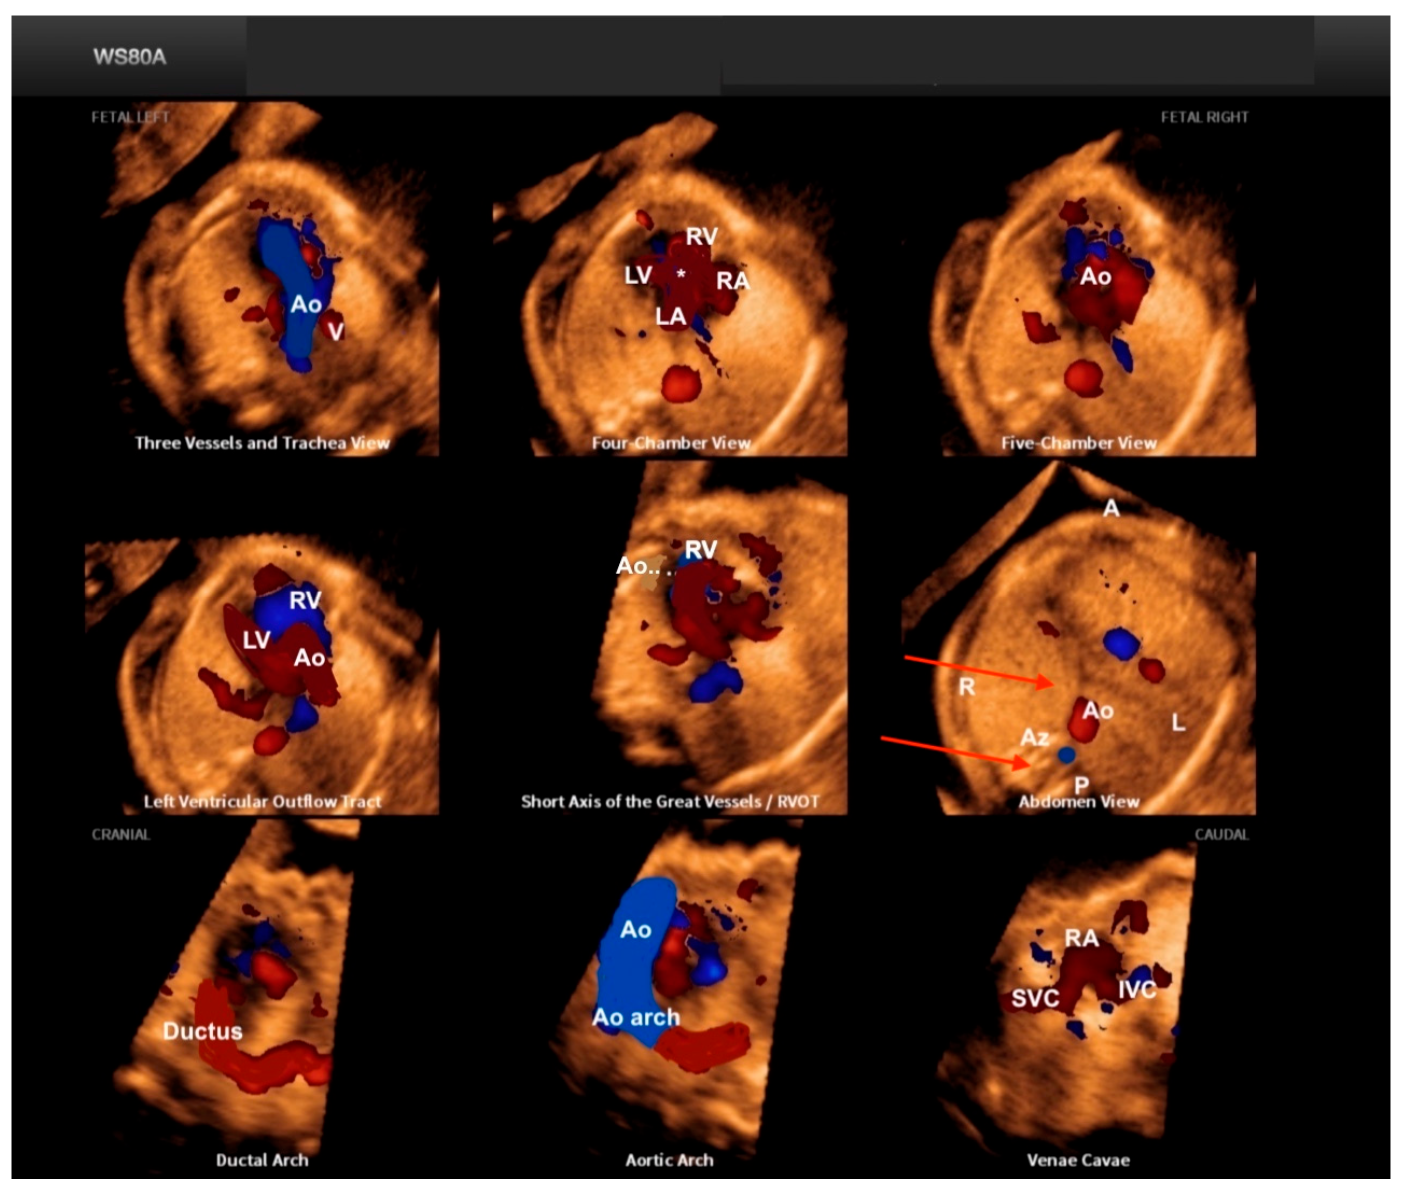

3. HDlive

4. Fetal Intelligent Navigation Echocardiography “5D Heart”

5. Realistic Vue, Crystal Vue, and LumiFlow